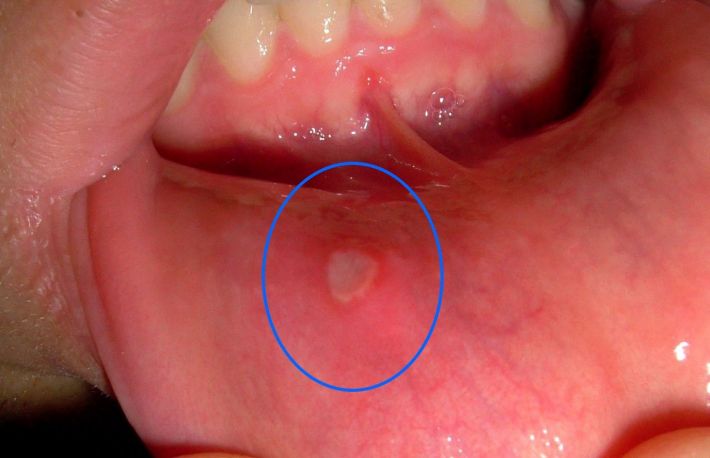

Umflaturile in interiorul gurii. Cancerul este caracterizat prin aparitia tumorilor sau a umflaturilor ce se formeaza in zona afectata. In prima faza, umflaturile sunt mici, pale si nedureroase, insa o data cu evolutia bolii, acestea dau o senzatie continua de usturime.

Petele albe si rosii in gura si pe buze sunt cel mai frecvent semn al cancerului oral, iar daca va confruntati cu asa ceva este indicat sa mergeti de urgenta la un consult medical.